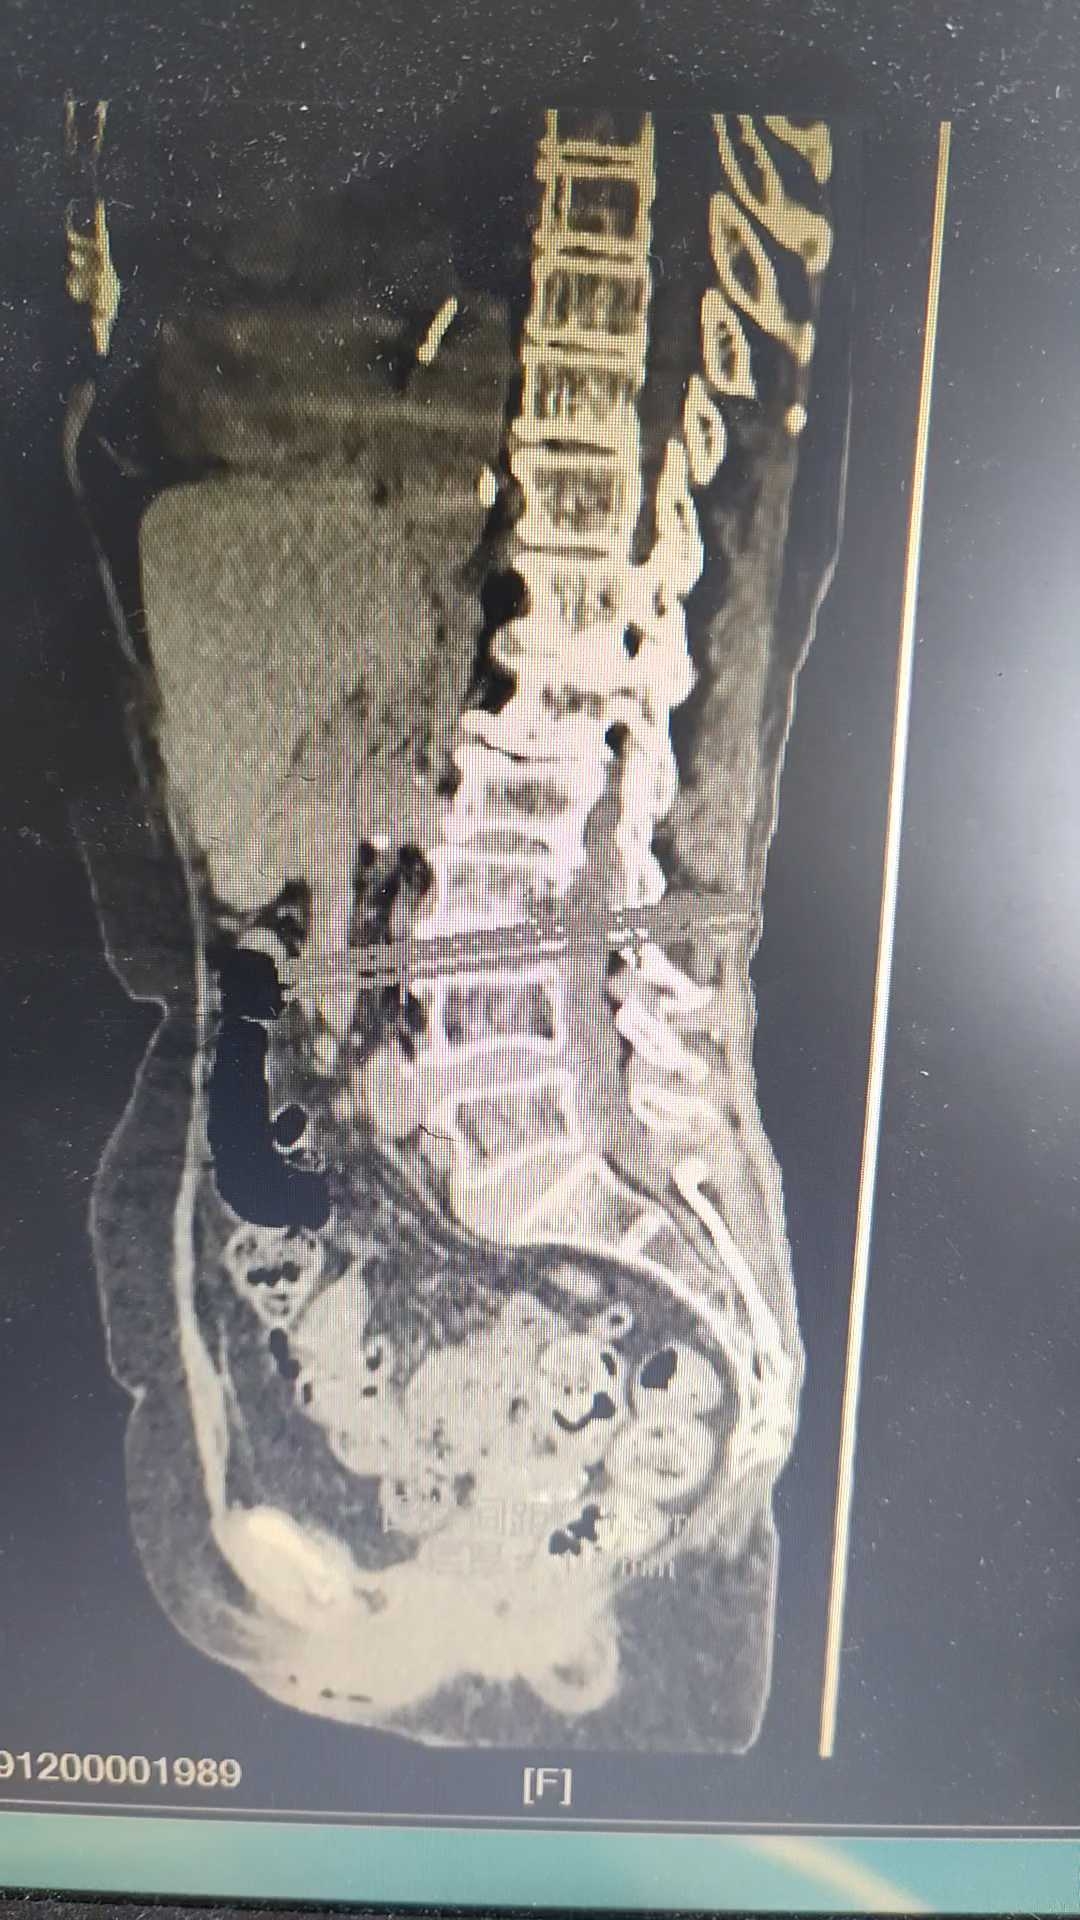

椎间盘CT示:

看到这些大家可能认为这就是腰椎间盘突出症,以腰L4/5突出为主。反复查体患者诉腰痛,改变体位时腰痛加重。